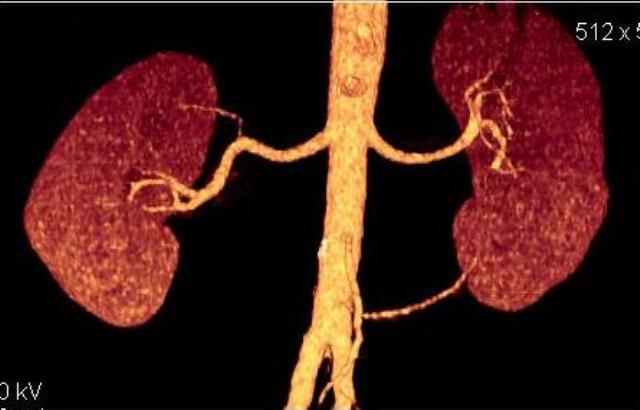

КТ Ангио почечных артерий.

Добавочные почечные артерии.

Справа добавочная артерия, питающая верхний полюс почки. Отходит от основного ствола почечной артерии. Слева дополнительная артерия, питающая нижний полюс почки, отходит от брюшной аорты, несколько выше бифуркации. В аорте видны атеросклеротические бляшки, одна из них довольно близко к устью добавочной артерии. Это может иметь клиническое значение.